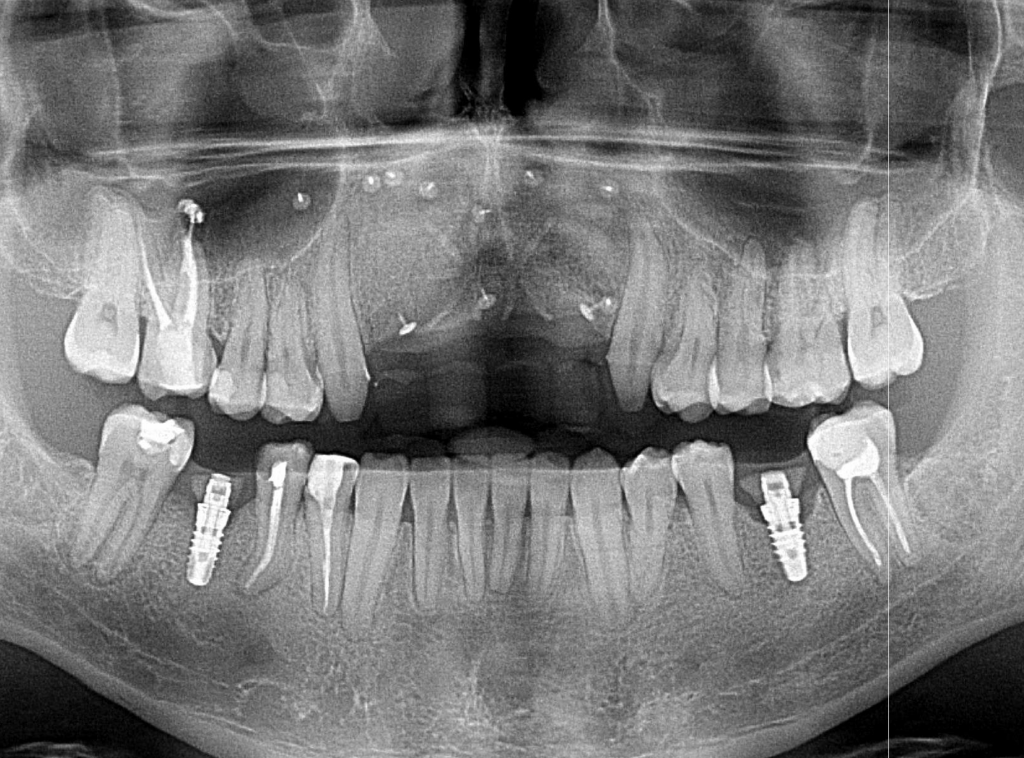

Szkolenie koncentruje się na przewidywalnych i bezpiecznych technikach augmentacji, w tym horyzontalnej i pionowej regeneracji kości, z dużym naciskiem na praktykę – uczestnicy wezmą udział w trzech warsztatach na preparatach zwierzęcych oraz zabiegach pokazowych (wideo), obserwując pracę doświadczonych wykładowców krok po kroku.

9:30 – 11:30 – Zabiegi na żywo lub VIDEO z zabiegów regeneracji kości.

W swojej pracy nie uznaje kompromisów i stosowania półśrodków – stawia sobie za cel wybór najlepszych w danym przypadku metod kompleksowego leczenia. Podejmuje się nawet najtrudniejszych zabiegów regeneracji kości, podniesienia zatok szczękowych, implantologii stosowanej, pełnej odbudowy uzębienia i przywrócenia prawidłowych funkcji żucia. Wszystko po to, by zapewnić Pacjentom spektakularny efekt zdrowego i pięknego uśmiechu.